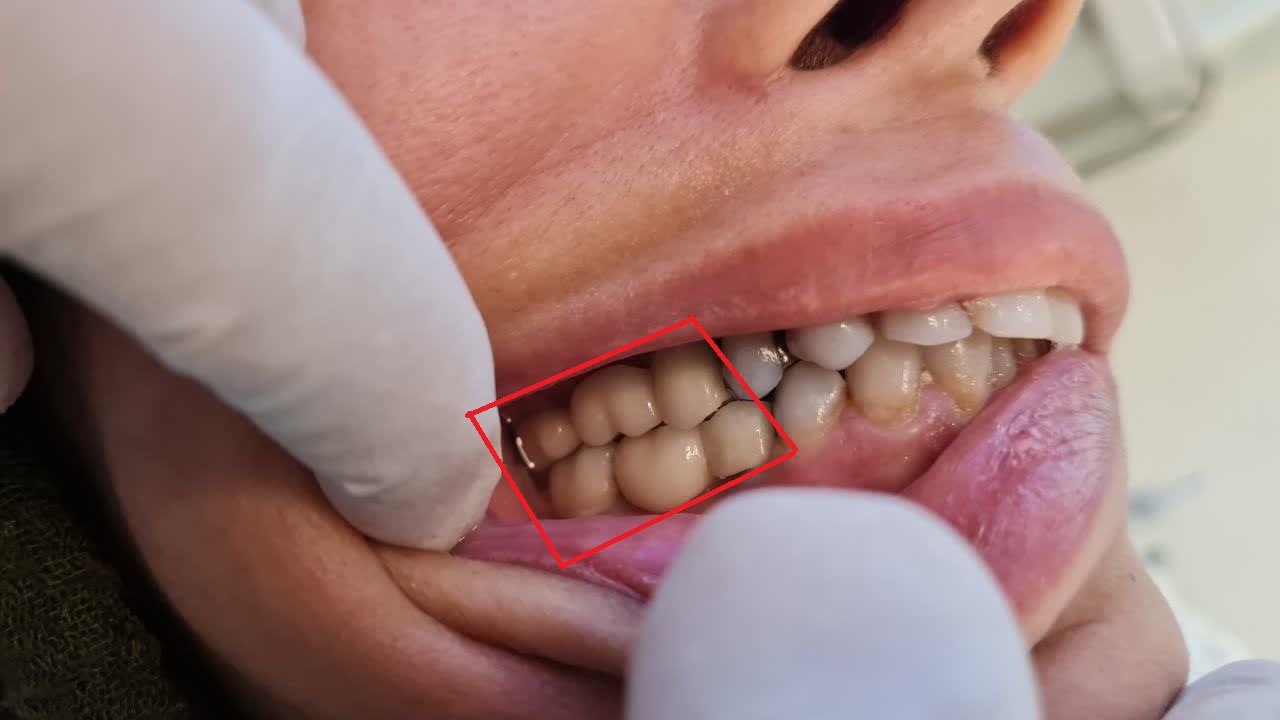

قرار دادن ايمپلنتهاي فک مقابل با همين روش

نتيجه كار بعد از روكشهاي زيركونيا